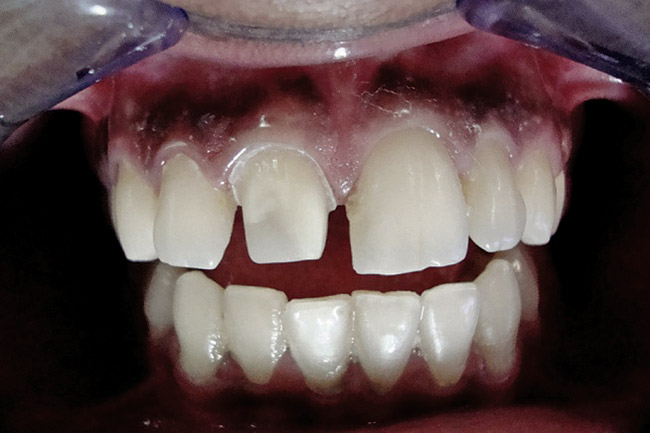

Figure 3  Placement of rubber dam with application of cervical clamp on central incisor for extra retraction.

Figure 3

Figure 4  Final composite restorations with respect to upper right incisors.

Figure 4